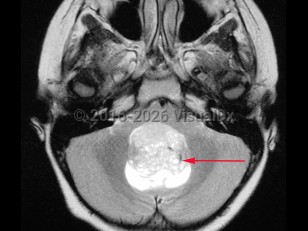

Medulloblastoma in Adult

A medulloblastoma is a malignant primary brain tumor located in the posterior fossa near the fourth ventricle. It is the most common malignant brain tumor in children. One-third of cases present in children aged younger than 3 years. In adults, the tumor usually presents before age 40.